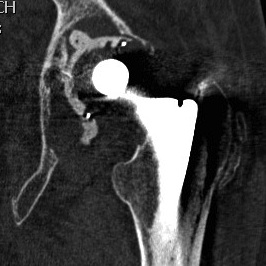

1. Loosening

2. Infection

3. Instability

4. Periprosthetic fracture